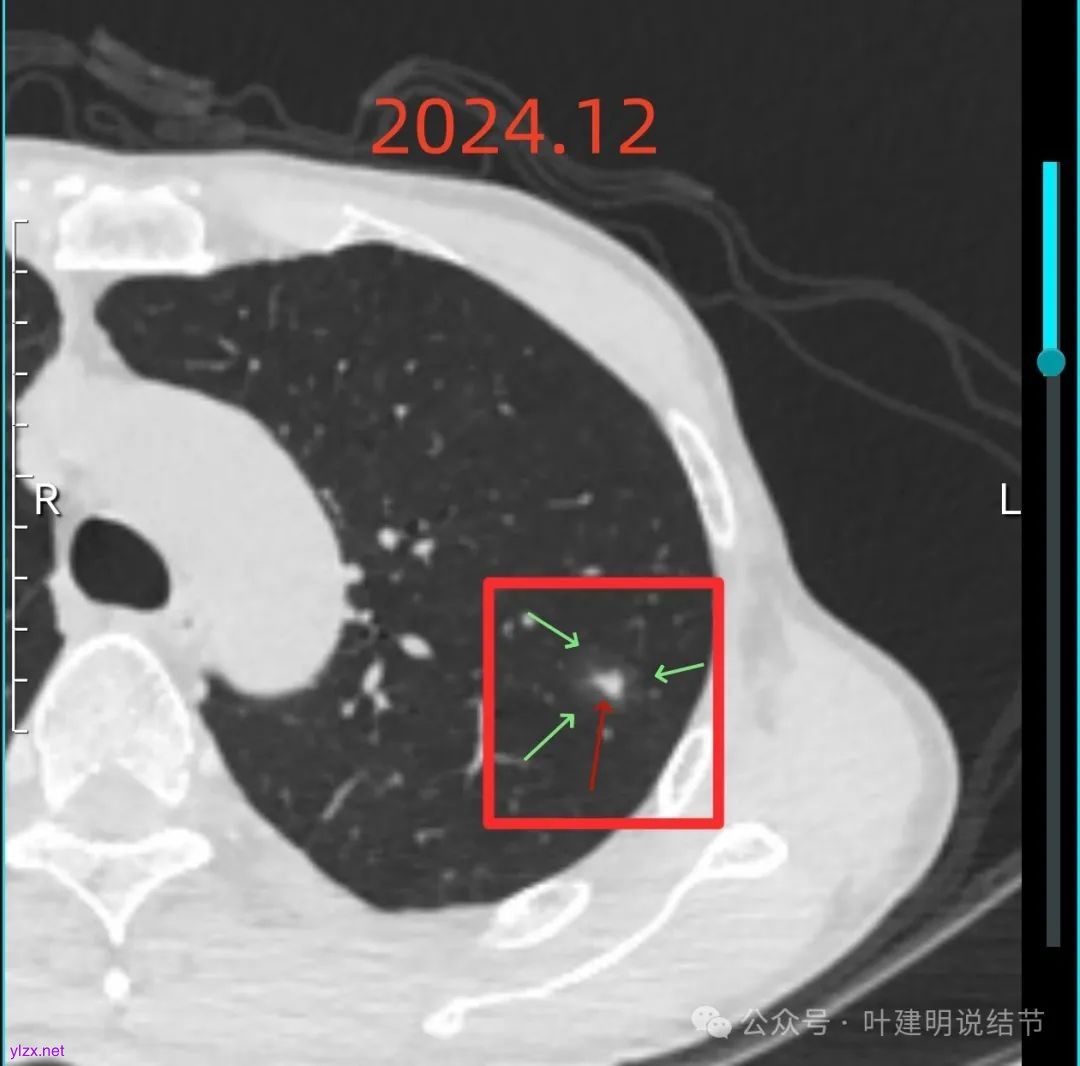

再来看2024年12月时的影像:

左上病灶血管进入了病灶且有异常增粗,边缘有淡的细毛刺的样子。

灶内血管明显,管壁略毛糙,有异常增粗,红色箭头处有点状高密度,边缘有毛刺征。

灶内出现了明显的实性成分,整体轮廓较清。

除了原血管进入外,另外角度也见到其他血管发出分支走向病灶,而且灶内密度不均,实性成分明显。